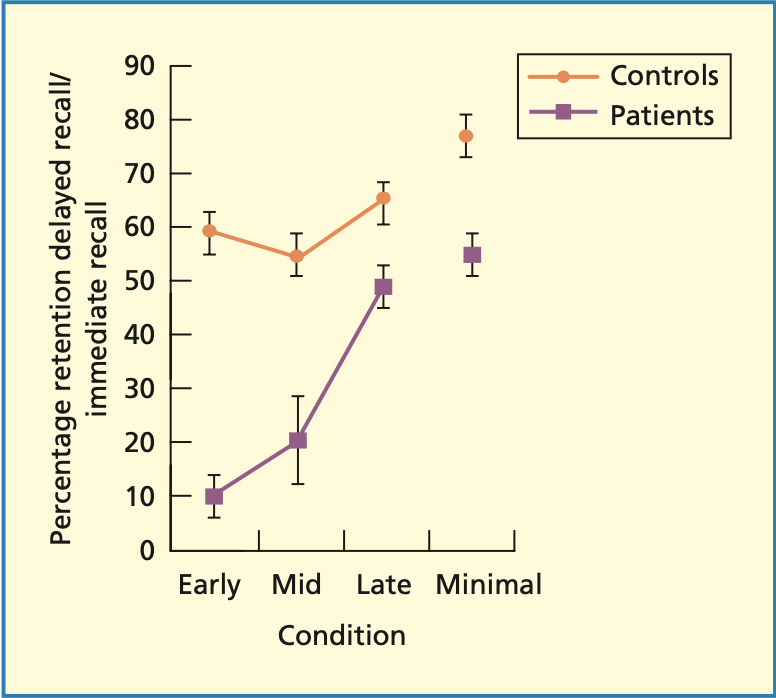

Konsolidierung bei Amnesie

Konsolidierung

Zeitliche Verflechtung von neuen Gedächtnisspuren mit bestehenden Gedächtnisinhalten

Konsolidierung bei Amnesie stärker anfällig auf Störungen

Retrograde Amnesie messen